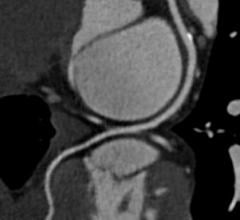

With headquarters in Tustin, Calif., Canon Medical Systems USA Inc. markets, sells, distributes and services radiology and cardiovascular systems, and coordinates clinical diagnostic imaging research for all modalities in the United States. Canon Medical Systems Corporation, an independent group company of Canon Inc., is a global leading provider of diagnostic imaging systems including CT, MRI, Ultrasound, X-ray systems and clinical laboratory systems. In business for more than 100 years, Canon Medical Systems Corporation (formerly Toshiba Medical Systems Corp.) was built to improve the quality of life for all people. It delivered on this mission with medical innovations that are “Made for Life”—made to improve the lives of patients, clinicians and administrators. Its legacy was built with pioneering medical technology, such as the world's first X-ray machines in 1932 and Japan's first magnetic resonance imaging (MRI) systems in 1983. Canon Inc. entered the healthcare business in 1940 with the development of Japan’s first indirect X-ray camera which was used for the early detection of pulmonary tuberculosis. The partnership of Toshiba Medical Systems Corporation and Canon (now Canon Medical Systems Corp.) brings together two cutting-edge technology businesses, founded with similar values of creativity, flexibility and patient-friendly healthcare solutions. Today, their combined history of research and innovation drive forward Canon Medical Systems’ vision for building a world-class healthcare enterprise. For more information: https://us.medical.canon/

Canon Medical Systems’ offering includes: computed tomography, magnetic resonance, ultrasound, X-ray, cath and EP lab